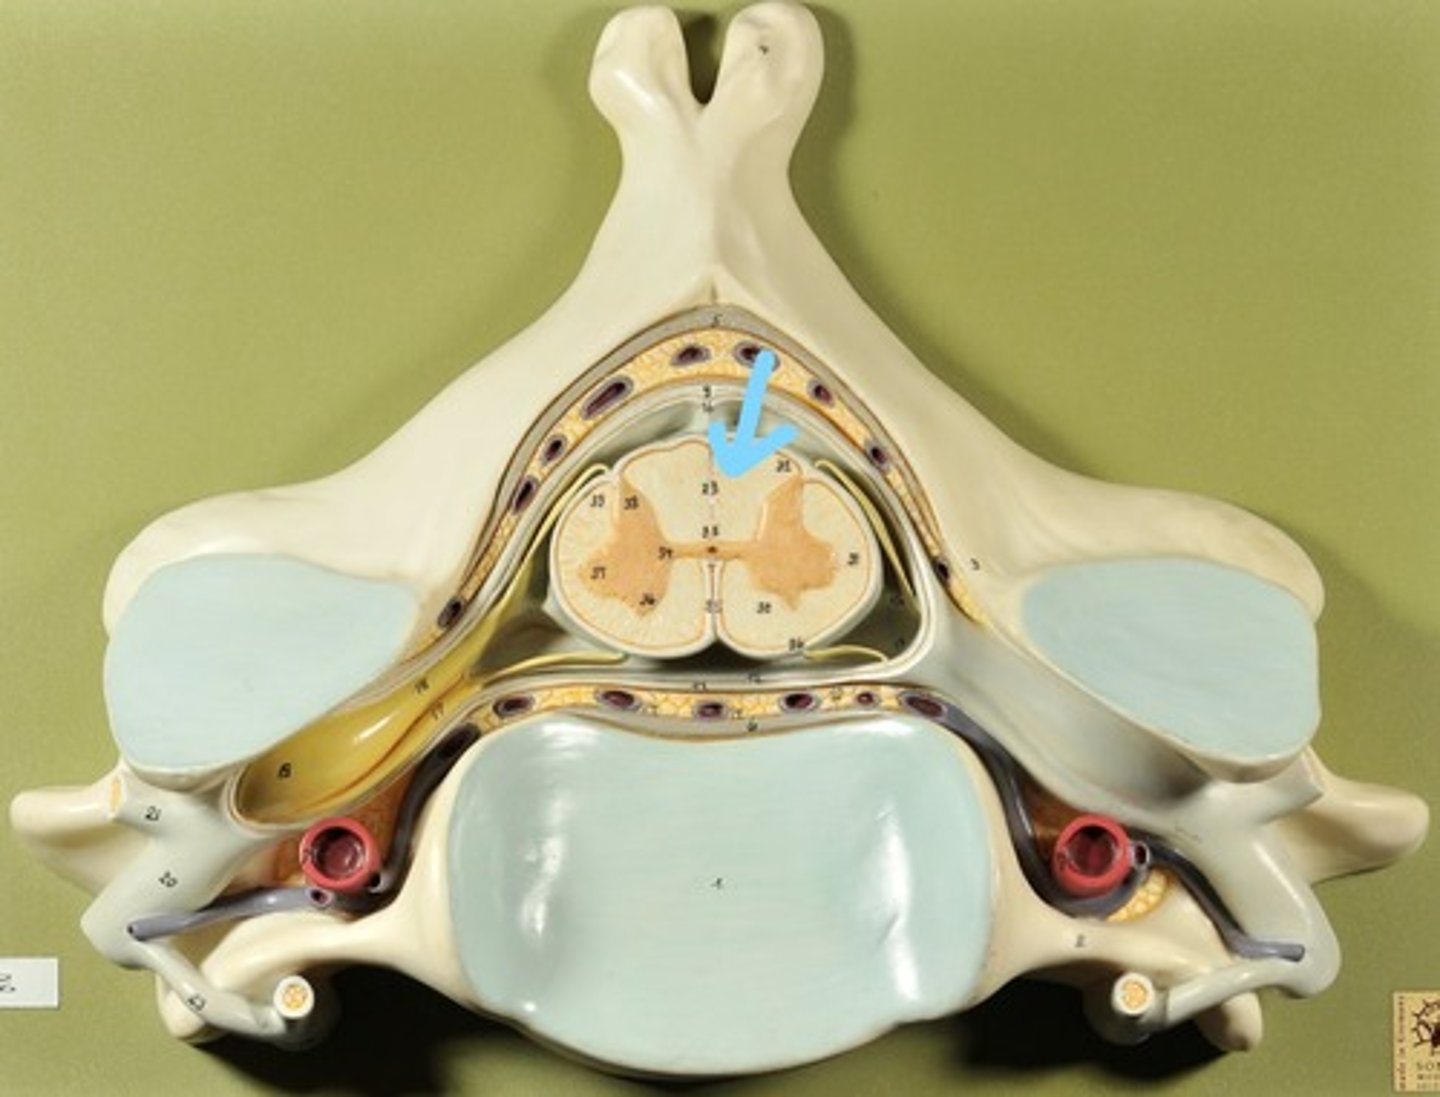

Identify all structures of spinal cord

White Matter of spinal cord

gray matter of spinal cord

Ventral Horns (gray matter)

Lateral Horns (gray matter)

Dorsal horns (gray matter)

Anterior Columns (white matter)

Lateral Columns (white matter)

Posterior Column (white matter)

central canal of spinal cord

Identify all structures

Pia Mater

Subarachnoid Space

Arachnoid mater

Subdural Space (brown line)

Dura mater

Epidural Space

Dorsal Root Ganglion

Dorsal Root

Ventral Root

Spinal Nerve